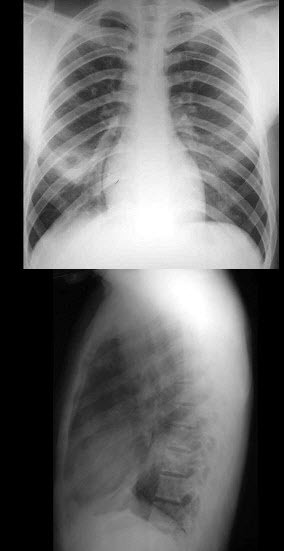

14、单项选择题 下列"脊柱转移瘤"特点,哪项正确()

男,45岁,发热、咳痰1月余,结合图像,最可能的诊断是()

A.肺脓肿

B.肺结核

C.吸入性肺炎

D.肺囊虫病

E.肺癌